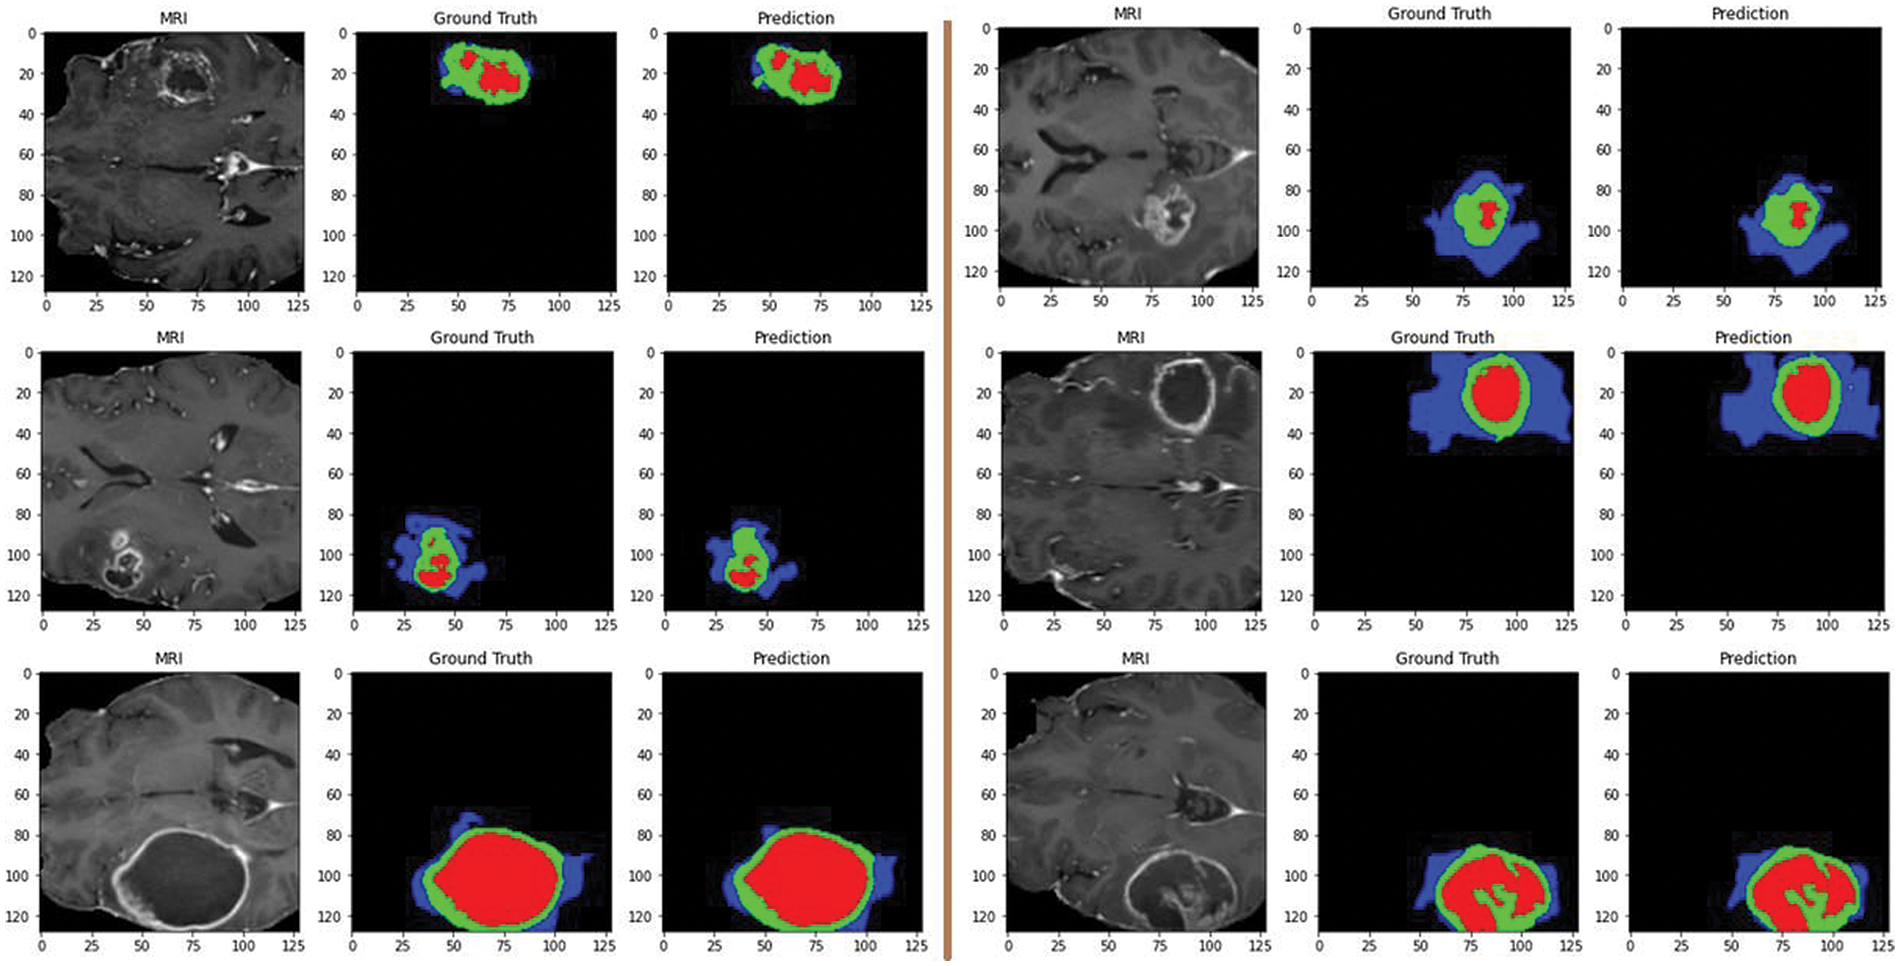

Additionally, Fig. 9 showcases predictions on testing images, demonstrating the model’s ability to segment different tumor regions accurately. In the figure, the core tumor is highlighted in red, the edema is shown in green, and the enhancing tumor is outlined in blue. These regions are crucial for precise tumor identification and classification. The combination of the core tumor, edema, and enhancing tumor regions represents the whole tumor, which a surrounding by black background area. This visual representation aids in understanding the model’s effectiveness in distinguishing and segmenting various tumor sub-regions, which is essential for accurate diagnosis and treatment planning.

Figure 9: Predictions on testing images by the proposed model: red for core tumor, green for edema, blue for enhancing tumor, and black for background